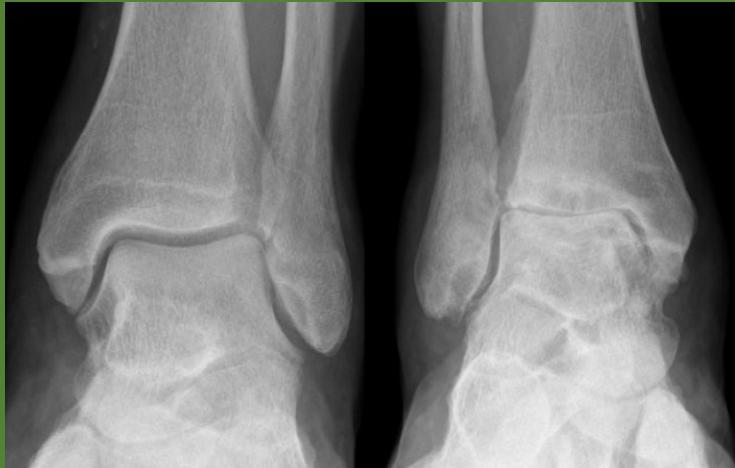

Imaging Studies

- Standard Radiographs:

- Both knees AP standing views (weight-bearing)

- Lateral views of both knees

- Skyline view (patellofemoral assessment)